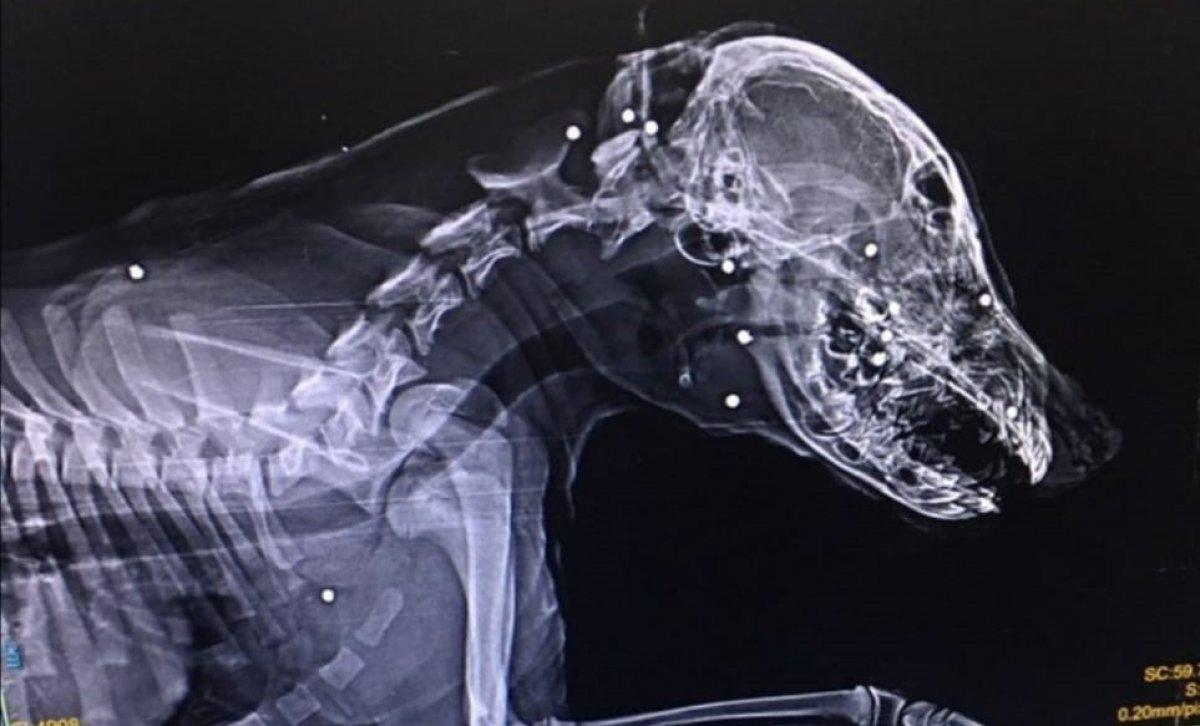

Devrek ilçesinde sahipli bir köpek, kimliği belirsiz kişilerce tüfekle suratından vurularak ağır yaralandı.

Zonguldak'ın Devrek ilçesinde Mert Ekşi’ye ait aylık sahipli köpek, kimliği belirsiz kişi veya kişilerce tüfekle suratından vurularak ağır yaralandı.

Tedavisi için köpeğini aracıyla Zonguldak'a götüren Ekşi’nin köpeğini vuran veya vuranlar için polis, geniş çağlı soruşturma başlattı.